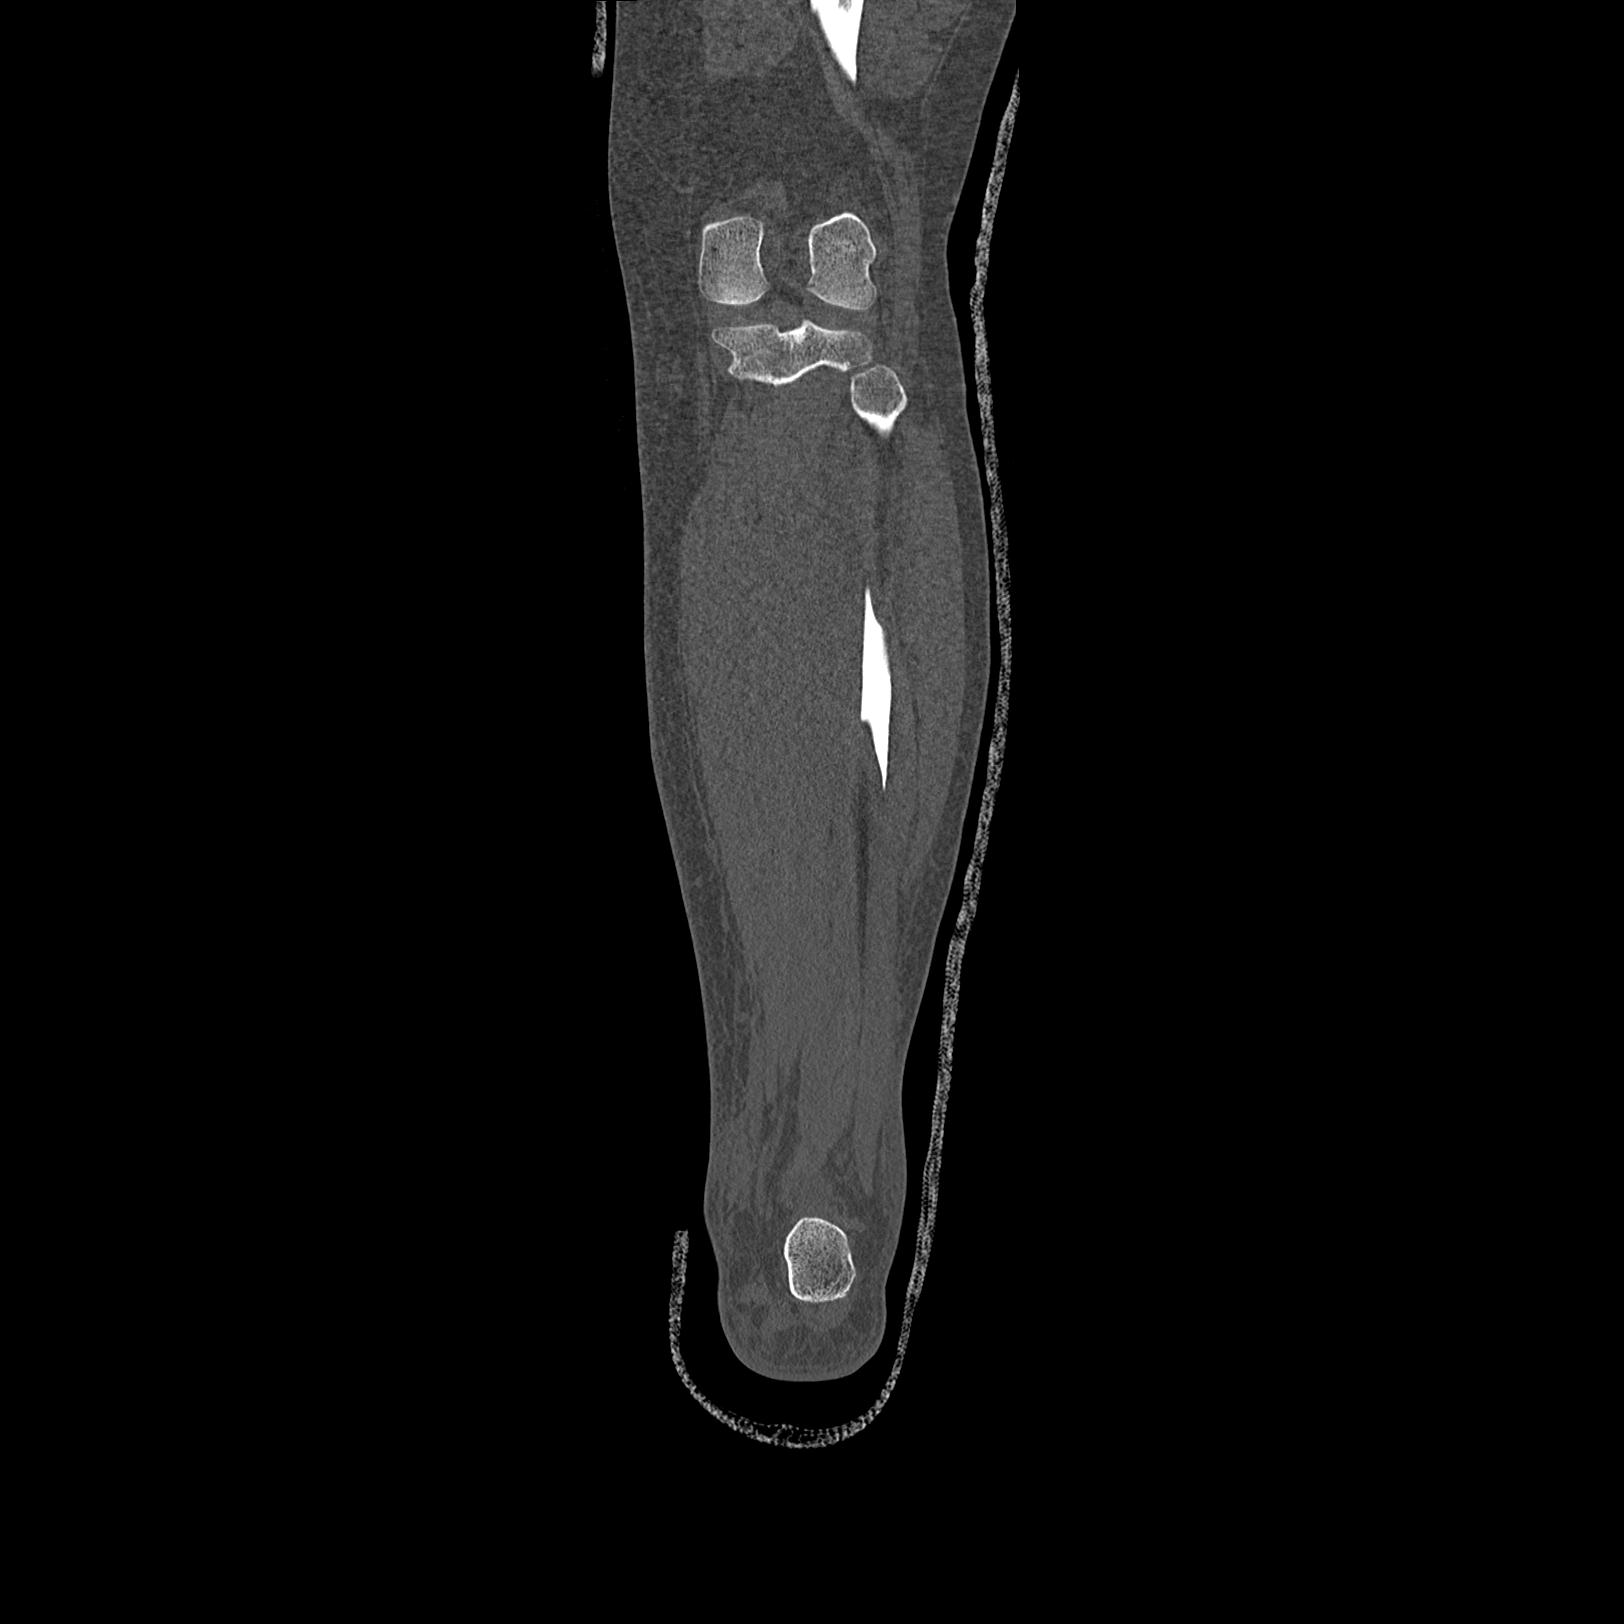

症例写真集

102803 1/12(キウスなし) 1/27 左下腿 4R 30歳女性 左脛骨軸内釘